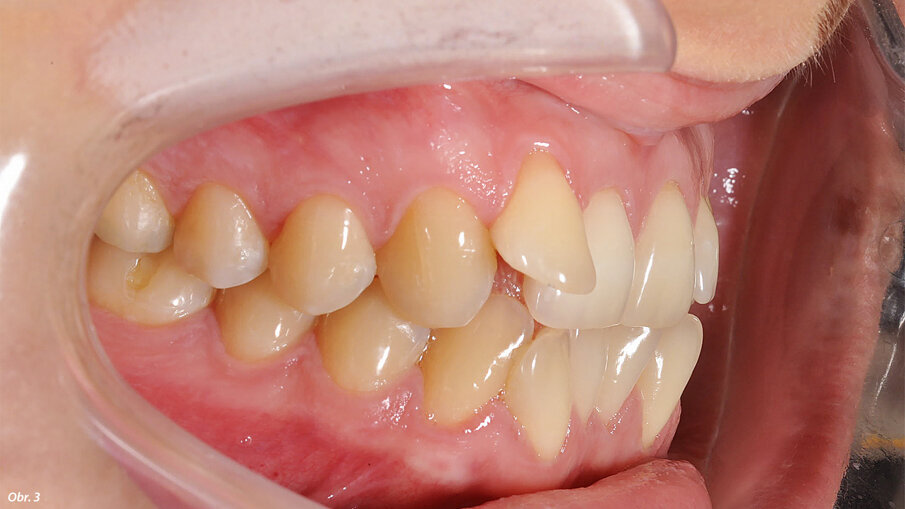

Vyšetřením jsme zjistili výrazný nedostatek místa v horní i dolní frontě. Zub 12, s meziodistální šířkou 6,25 mm, byl eruptován vestibulárně zcela mimo zubní řadu se současným posunem horní středové linie doprava. Mezera mezi zuby 11 a 13 činila 1,5 mm. Nedostatek místa v dolním zubním oblouku činil 2,6 mm resp. 2,85 mm ve dvou dolních kvadrantech. V transverzálním rozměru byl oproti normě menší jak anteriorně, tak i posteriorně. Oproti tomu skus laterálně a v místě špičáků byl normální – zde jsme diagnostikovali I. třídu podle Anglea. Hloubka skusu byla 0,5 mm s tendencí k otevřenému skusu. Incizální schůdek byl 0 mm se skusem hrana na hranu u zubů 11/41 a 21/31/41. Podle Boltnových indexů byl přítomen nepoměr v šířce zubů s přebytkem „zubního materiálu“ v dolní čelisti (obr. 3–5). Při skeletální diagnostice jsme nalezli disharmonii ve velikosti čelistí s retrognátní horní čelistí a ortognátní mandibulou – III. skeletální třída s úhlem ANB -2,3° a hodnotou WITS o velikosti -3,9 mm. U vertikální analýzy byl zřejmý mírně horizontální typ růstu s hodnotou SpP/MeGo 23° a poměrem SGo/NMe 71 % na základě anteriorní inklinace horní čelisti. Interincizální úhel byl lehce zvětšený, což bylo dáno mírnou protruzí horních řezáků spolu s retrudovaným postavením dolních řezáků (obr. 6, 7).

EIntraorální fotografie počátečního stavu pacientky.

Horní řezáky jsou mírně protrudované, dolní řezáky mírně retrudované.